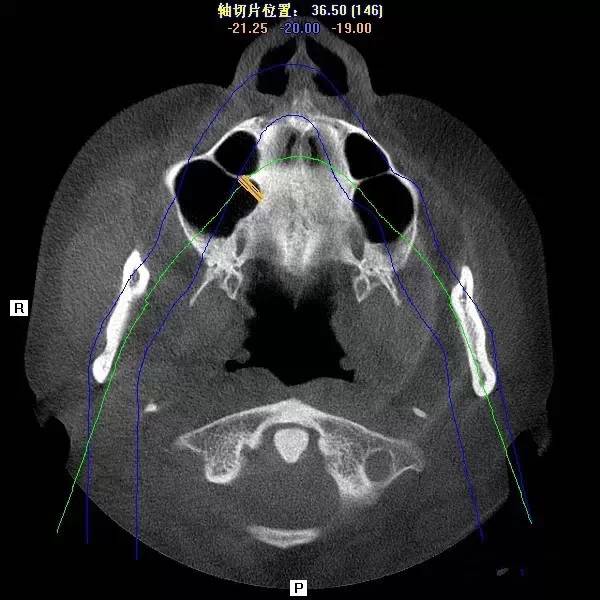

第四圖:上頜竇發(fā)育不足,上頜竇底骨高度充裕,通常頰側(cè)骨壁超級厚,看下圖2.臨床上種植常不需要提升措施。(如需提升,切記頰側(cè)骨厚度過大,開窗的困難性劇增)